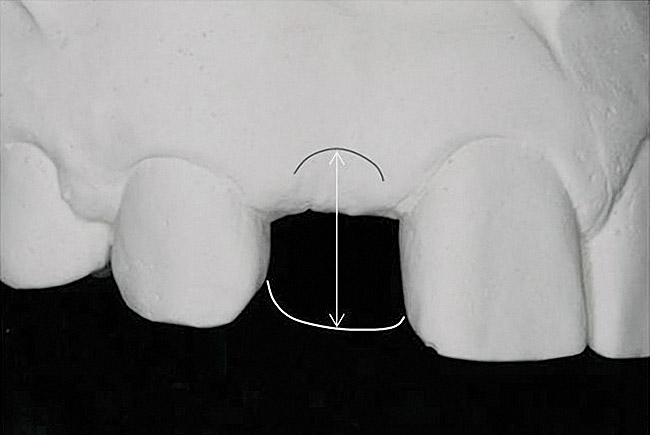

Figure 1  Critical bone and soft tissue relationships: The position of the buccal bone crest is approximately 3 mm from the gingival zenith of the natural tooth. Recapitulation of this architecture for ideal single-tooth implant esthetics requires that the adjacent bone crest approximate this level in three dimensions. Implant placement at the crest will support the formation of 3 mm of supracrestal buccal soft tissue, which embodies the suclus and the junctional epithelium/connective tissue contact along a titanium or zirconia abutment.

Figure 1